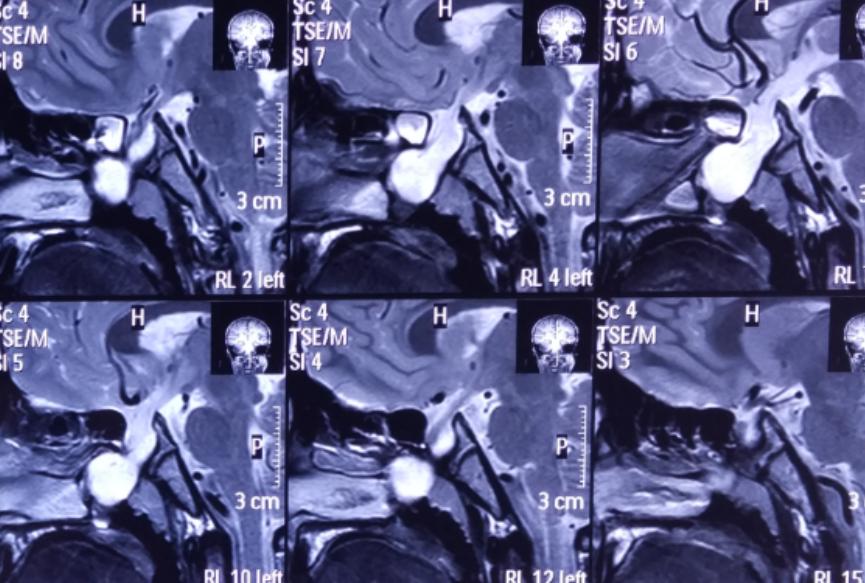

影像资料